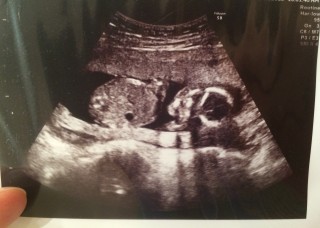

初めての体外受精で授かり、大量出血で切迫流産になり7~12wを寝たきりで過ごし、初めて4wあけての検診でした。背骨や肋骨もキレイ!!問題なく診察終わって看護師さんから「可愛いですね」と手渡されたエコー写真。何となく笑顔で手を振ってるような…(笑)今から親バカです(^^)